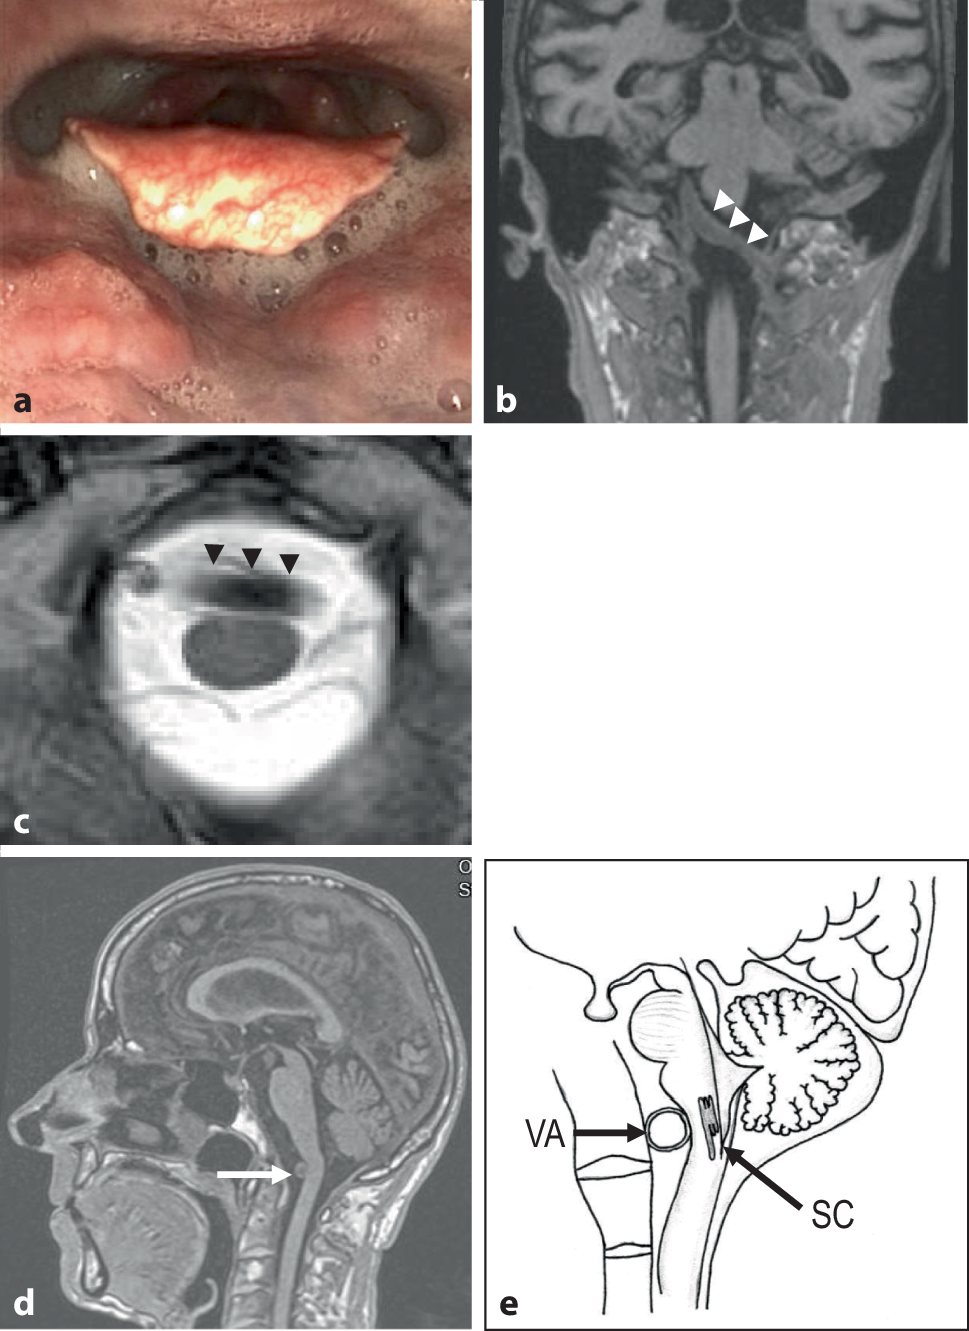

An 80-year-old patient reported unwanted weight loss of 20 kg and difficulty swallowing for 2 years. He also had to cough frequently when eating. In the neurological examination there were no definite deficits of the cranial nerves. The tongue had a strong muscle relief, no definite fasciculations, the soft palate was well elevated, the pharyngeal reflex could be triggered laterally. The voice sounded slightly labored. There was no limb paresis and no ataxia. No fasciculations were visible or provocable. The muscle reflexes were equal. There were no pyramidal tract signs. Standing and walking in the room were unremarkable. Neuromuscular testing and the antibody profile showed no myasthenia gravis. The patient did not have arterial hypertension. There were also no anamnestic or clinical hints of a congenital disorder such as Marfan syndrome or Fabry disease. Gastroscopy and ear, nose and throat examinations were unremarkable. Dynamic pharyngoesophagography revealed delayed swallowing reflex triggering and reduced elevation and ventral movement of the hypolaryngeal complex. Fiber endoscopic evaluation of the act of swallowing (FEES) showed spontaneous accumulation of saliva in the hypopharynx, valleculae and piriform sinus (Fig. 1a). In addition, moderate vallecular residue by two consistencies (solid, pureed) and a postdeglutitive aspiration were present. Cranial MR-tomography using an open 1 T scanner demonstrated an enlarged transverse left vertebral artery (dolicho-vertebral artery) at the level of the foramen magnum with dorsal compression and slight kinking of the medulla oblongata (Fig. 1b–d). Neurogenic dysphagia due to compression of the medulla oblongata by the left enlarged and enlongated vertebral artery was diagnosed. As the patient refused neurosurgical decompression swallowing therapy was instructed.

a Snapshot during fiber endosopic examination of the swallowing (FEES) with pronounced accumulation of unswallowed periepiglottic saliva. b Coronar T1-weighted magnetic resonance imaging (MRI) with enlarged and elongated left vertebral artery (white arrowheads) crossing and displacing the medulla oblongata. c Axial T2-weighted MRI with enlarged transverse vertebral artery (black arrowheads) leading to touching and compression of the medulla oblongata. d Sagittal T1-weighted MRI in the midline. The transverse crossing vertebral artery (arrow) displaces the medulla oblongata and bends it slightly. e Schematic drawing of the proposed pathophysiological mechanism by sagittal view on the midline brainstem. The enlarged vertebral artery (VA) compresses the brainstem at the level of the dorsal and ventral swallowing centers (SC)